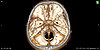

В КОКБ пациент был дообследован: в кратчайшие сроки проведена компьютерная томография головного мозга, которая показала разрыв мешотчатой аневризмы средней мозговой артерии слева, что и стало причиной кровоизлияния. Как рассказал врач-нейрохирург Денис Старков, пациент находился в тяжёлом состоянии, у него уже отсутствовала речь, требовалась срочная операция. Незамедлительно пациенту было выполнено оперативное вмешательство – костно-пластическая трепанация черепа и клипирование аневризмы средней мозговой артерии слева. Это позволило выключить ее из кровотока для предотвращения повторного разрыва и кровоизлияния.

– За 27 лет нейрохирургия шагнула далеко вперёд, методики и подходы и к хирургическому лечению аневризм головного мозга значительно изменились. Это наглядно видно даже по контрольным снимкам конкретного пациента: в первый раз вмешательство проходило с использованием бинокулярной лупы через большой доступ в черепе. Сегодня в арсенале хирургов - новейший нейрохирургический микроскоп, поступивший в КОКБ в рамках нацпроекта «Здравоохранение». Совершенствуются доступы к структурам головного мозга. Все вмешательства выполняются через небольшие отверстия, безопасно и малотравматично, - подчеркнул завотделением.

3. До операции

3. После операции